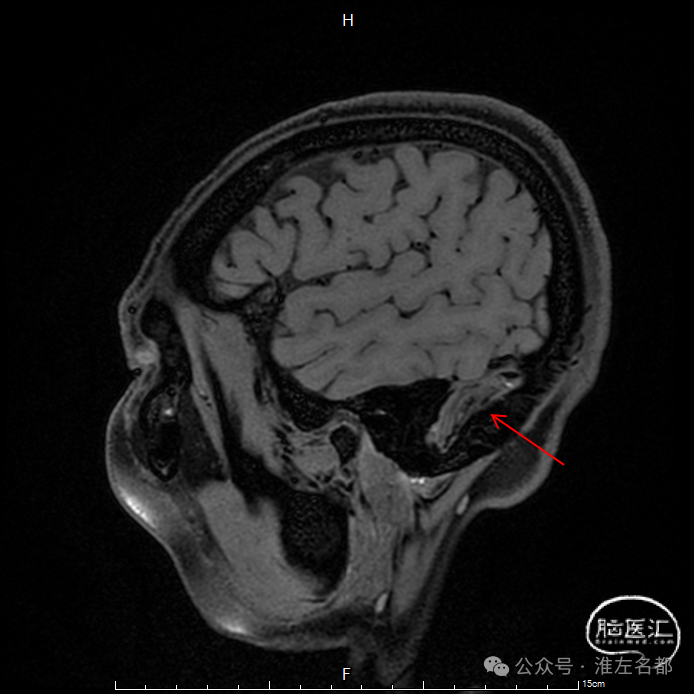

三维黑血高分辨T1平扫(上图)和增强(下图):右侧乙状窦慢性血栓,平扫呈等低信号,并显著强化。

三维黑血高分辨T1平扫(上图)和增强(下图):右侧横窦慢性血栓。

三维黑血高分辨T1平扫(上图)和增强(下图):上矢状窦慢性血栓;直窦内新进血栓(急性血栓等低信号,或亚急性血栓高信号,无强化)。

三维黑血高分辨T1平扫(上图)和增强(下图):左侧横窦发育细小。

三维黑血高分辨T1平扫(上图)和增强(下图):左侧乙状窦局部未发育。